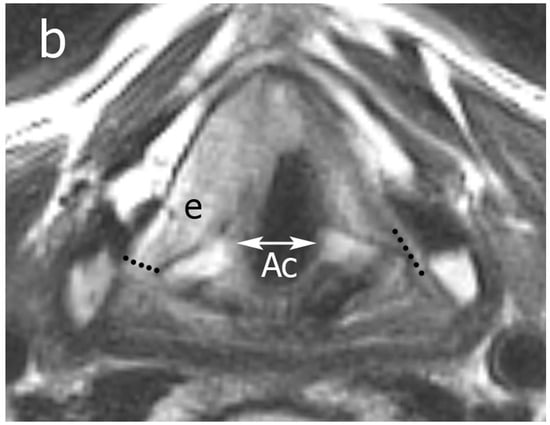

Figure 1.

Anatomical section representing the glottic plane on a transverse section: dashed line (“magic plane” according to Succo et al. [4]) indicates the limit dividing the anterior (green) from the posterior (red) laryngeal compartments. Legend: Ac, arytenoid cartilage; tc, thyroid cartilage; vm, vocal muscle.